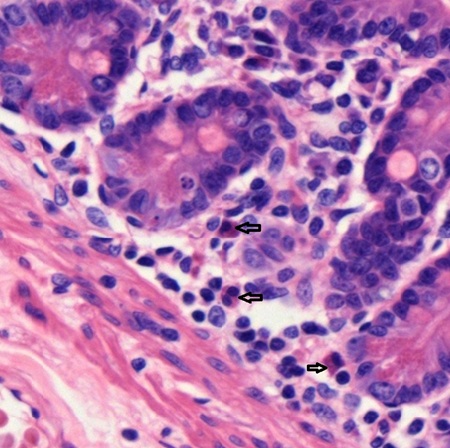

The majority of eosinophils (arrow) are only present in blood for hours then enter the skin (Fig. 5-23), mucosa of pulmonary tract (Fig. 5-24), and gastrointestinal tract (Fig. 5-25) in response to injury or bacterial invasion.